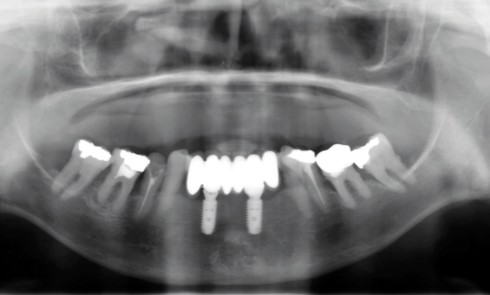

Article réservé à nos abonnés Gestion d’une complication implantaire d’une réhabilitation par prothèse composite

L’association d’implants à la prothèse amovible partielle (PAP) est de plus en plus fréquente et permet de répondre à de...